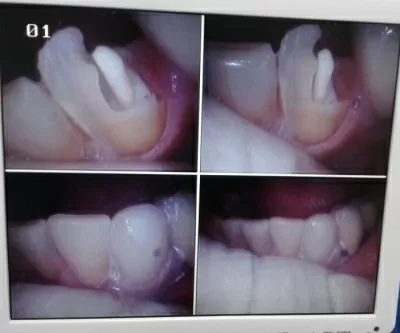

С лета 2018 лечусь в клинике Лигадент у доктора Трошян Тиграна Гамлетовича. За это время доктор восстановил мне все зубы, при лечении которых ранее были допущены, мягко говоря, ошибки. Произвел впечатление очень ответственного, грамотного, образованного специалиста с большим опытом, Это настоящее счастье, когда с тобой работает профессионал такого уровня! Далее мне поставили читать далее